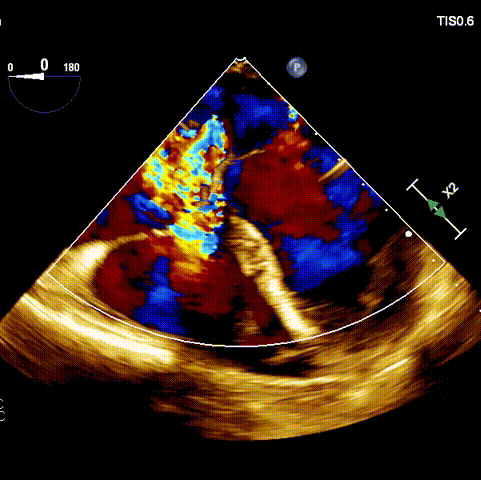

術(shù)前超聲

接受手術(shù)的為一名80歲男性,因“心悸2年,氣喘伴下肢水腫半年”入院。超聲心動(dòng)提示“極重度三尖瓣反流,右房及右室明顯擴(kuò)大,右心收縮功能輕度減低,左心收縮功能正常,肺動(dòng)脈壓力正常”?;颊咄瑫r(shí)合并有“持續(xù)性房顫”及“慢性心力衰竭”,病史持續(xù)2年,規(guī)律口服抗凝及強(qiáng)心、利尿治療治療效果不佳,癥狀持續(xù)。經(jīng)廈心心臟團(tuán)隊(duì)評(píng)估后,認(rèn)為患者三尖瓣極重度反流并伴有心衰表現(xiàn),長(zhǎng)期內(nèi)科藥物治療效果不佳,且患者高齡、外科手術(shù)風(fēng)險(xiǎn)高,因此決定采用微創(chuàng)經(jīng)頸靜脈LuX-Valve Plus三尖瓣置換系統(tǒng)為患者治療。